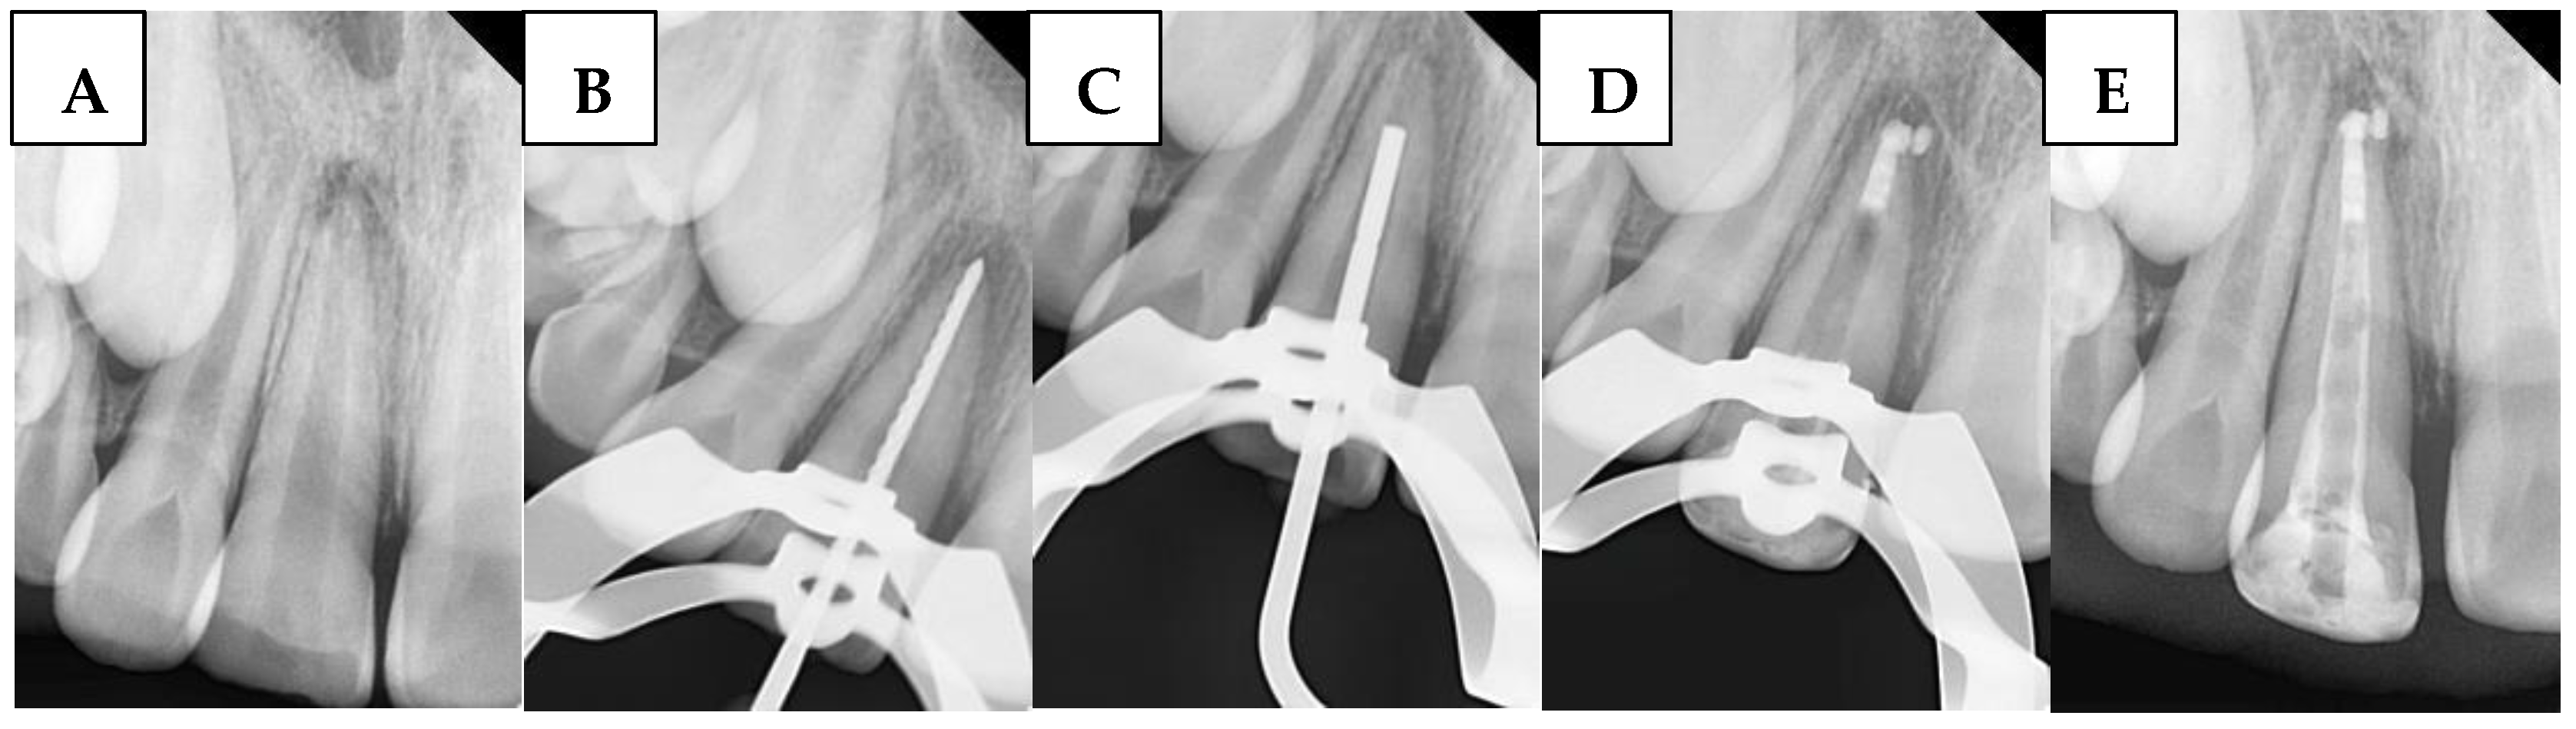

2.6.4. Single Cone Gutta-Percha with BioCeramic Sealer (SBS) Group

A large-sized (#80, taper of 2%) gutta-percha cone (GC) was inserted. The GC was trimmed to fit the canal width as closely as possible without exceeding the WL. The GC was ensured to make tag-back with the apical third of the immature canal and confirmed with a periapical radiograph. Afterward, it was removed, and the immature canal was gently obturated with BS with an adequate amount, and the GC was inserted again, and another apical radiograph was taken to confirm that the canal was properly filled without gaps and voids. Any BioCeramic extrusion was recorded at this stage in the DPF. Figure 3 illustrates the steps of the procedure in the SBS group.

Figure 3. Sequential steps of the procedure in the SBS group: (A) Preoperative periapical radiograph, (B) Working length radiograph, (C) Cone fit, and (D) Postoperative radiograph.